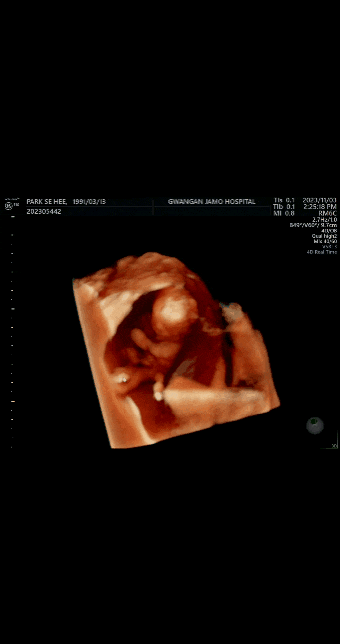

[임신 16주차] 임산부 편두통 증상, 보건소 철분제, 2차기형아검사

부쩍 좋아진 체력이지만 또 다른 증상이 생겼다 바로 편두통!!! 약간의 빈혈도 생겼다 하지만 이것은 지극...

[임신 14주, 4개월차] 안정기 진입, 임산부 일반 병원 진료비 할인

먹덧도 사라지고 입덧도 사라진 요즘 화장실가는 빈도수도 이전보다 많이 줄고 배 불편함도 줄고 허리통증...

[임신 11주차, 3개월] 증상(허리통증, 부종) 및 증상완화 꿀팁, 1차기형아검사

10주차때부터 아팠던 허리가 나아지나 싶었는데 기침 한방에 물거품이 되어버렸지요 임산부 허리통증 다행...